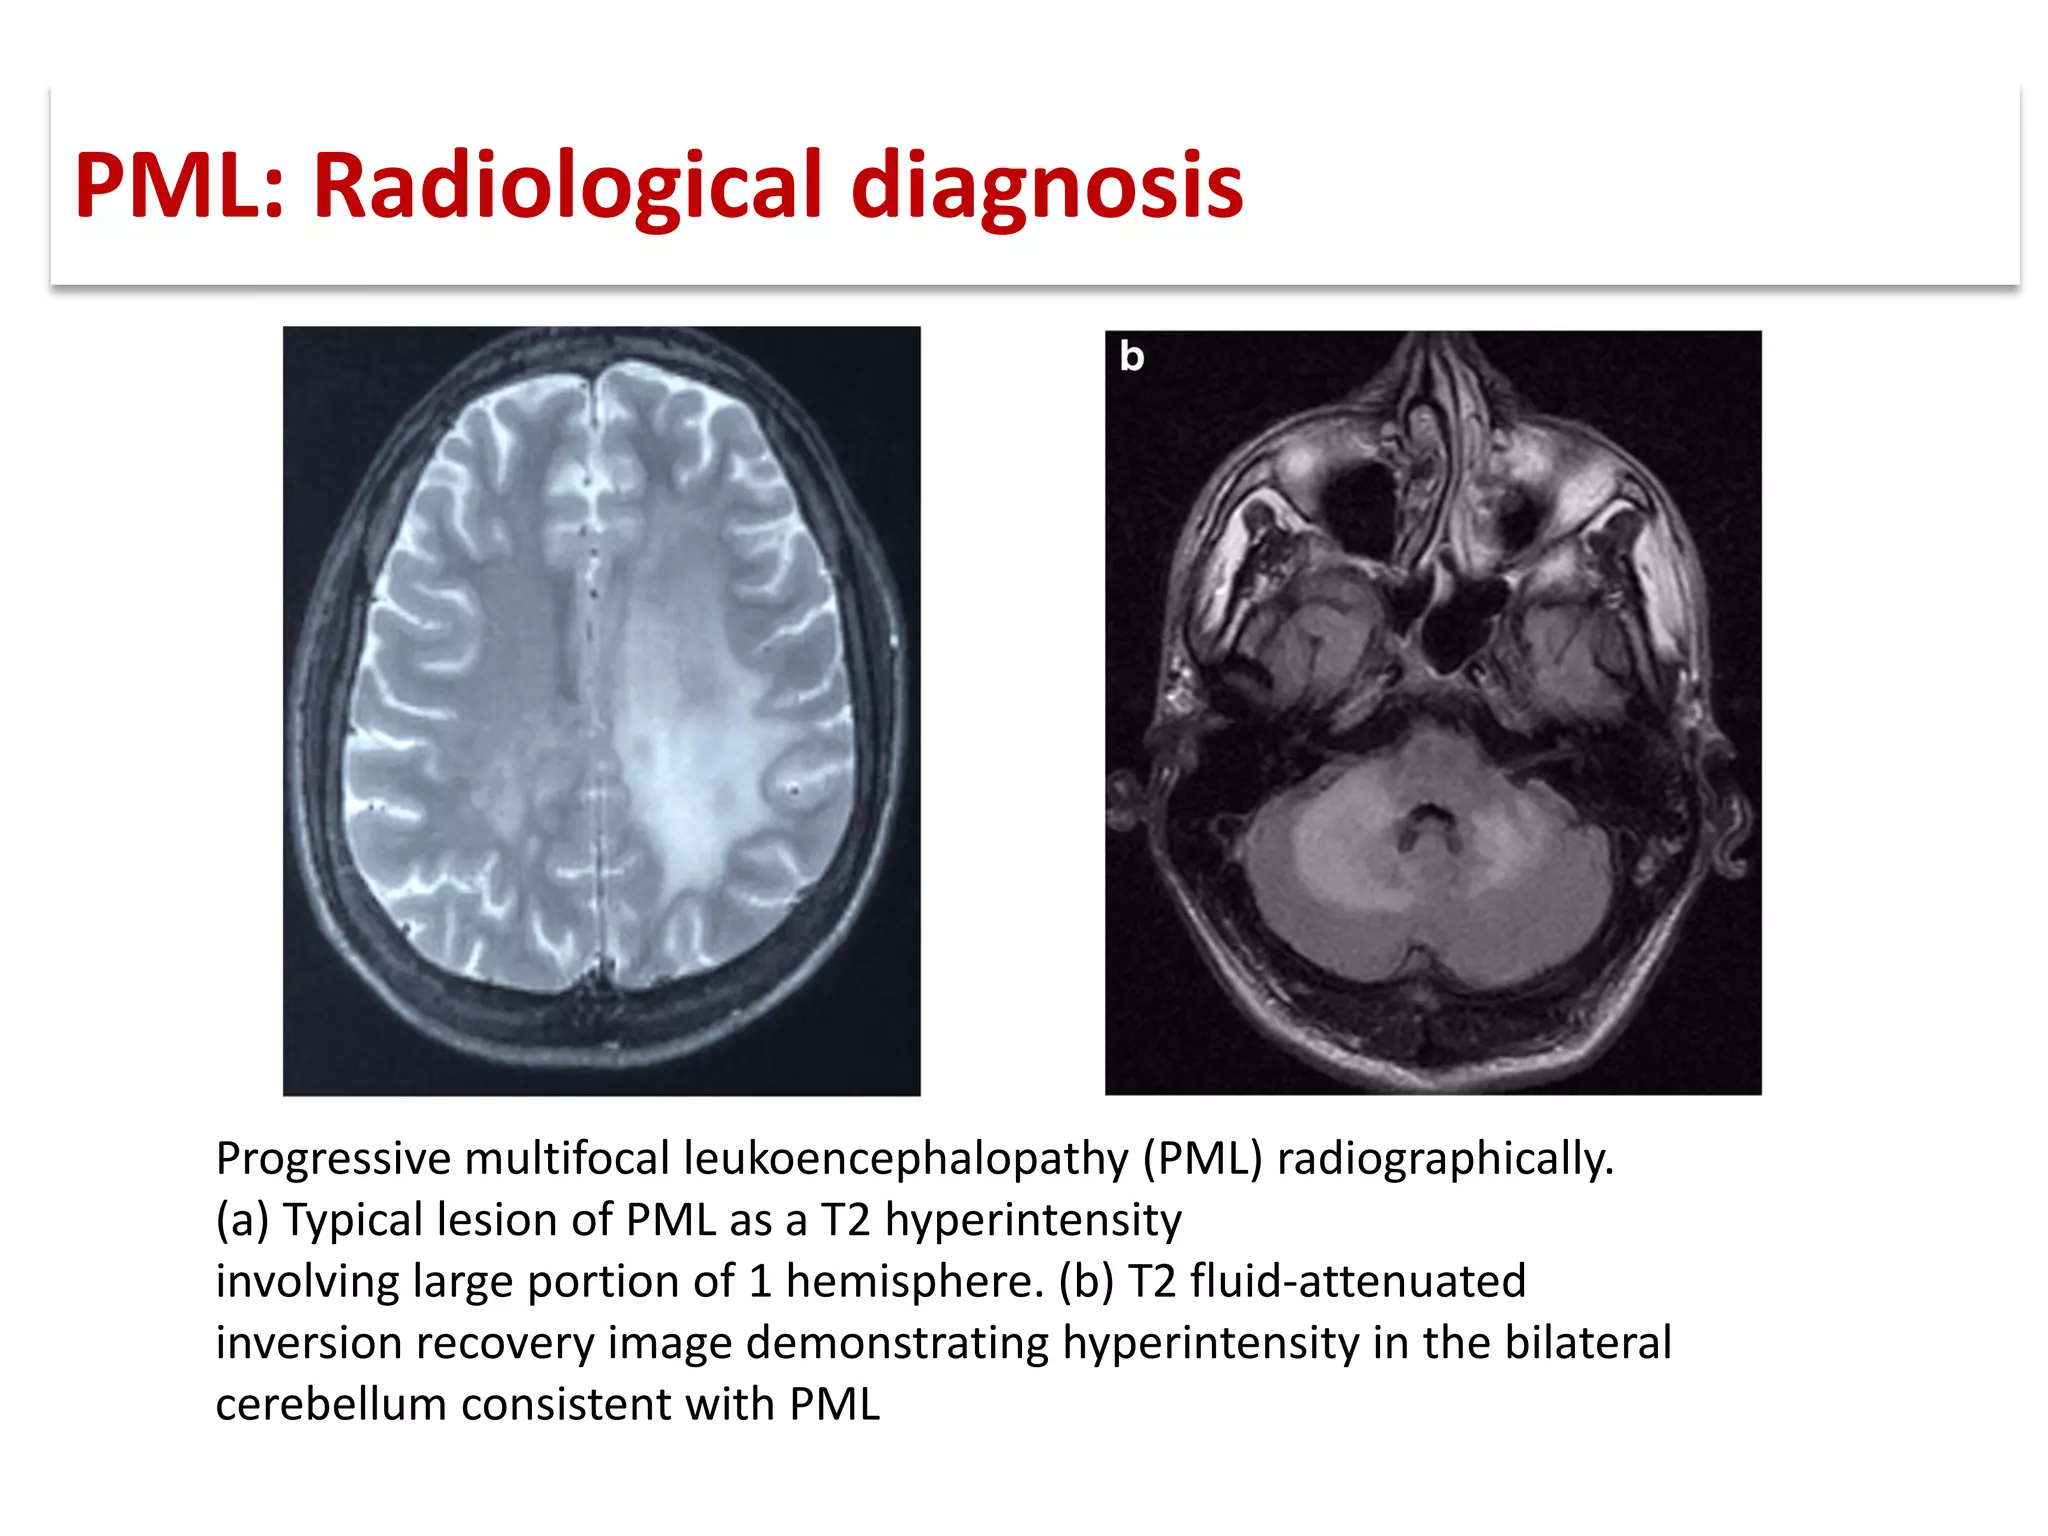

This document discusses progressive multifocal leukoencephalopathy (PML), an opportunistic infection caused by the John Cunningham virus (JCV) that leads to demyelination in the central nervous system. It highlights the epidemiology, clinical manifestations, diagnostic methods, and risk factors associated with PML, particularly in immunocompromised patients and those undergoing immunomodulatory therapies. It also presents data on the incidence of PML in patients treated with natalizumab and other therapies, addressing the relationships between these treatments and the development of PML.